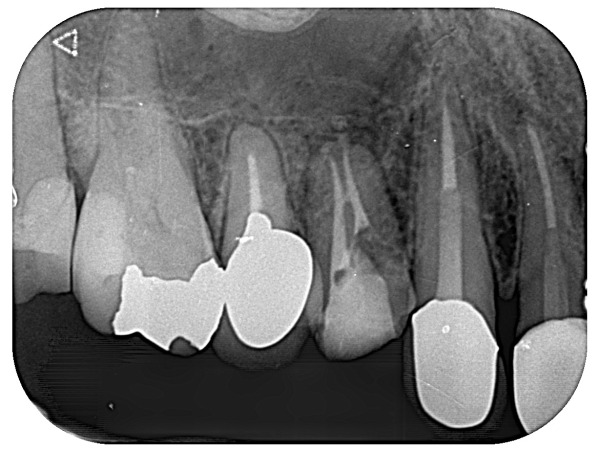

こちらが術後のレントゲン写真になります。

メインの2つの根管だけでなく、間にある側枝と呼ばれる通路にまでお薬が入ったことがわかります。

患者様は「噛むと痛い」という術前の症状が消えました。またレントゲンで根の先にあった黒い影も改善傾向を認めてきています。